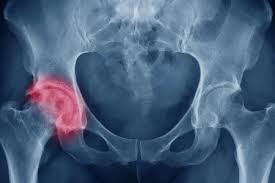

ساییدگی مفصل ران نشانه چیست؟

مفصل ران یکی از بزرگ ترین و حیاتی ترین مفاصل بدن است که نقش کلیدی در حرکت و تحمل وزن…